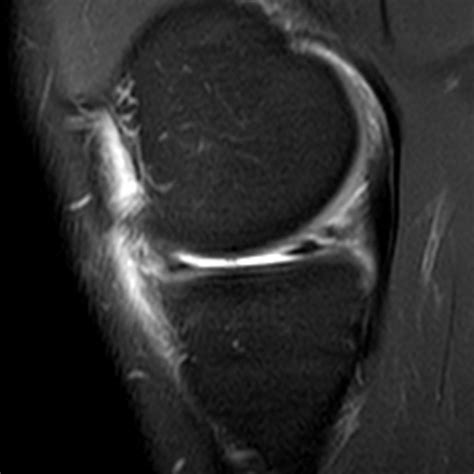

| MRI Scan | Provides elaborated images of soft tissue to confirm the tear location and pattern. |

⚠️ Tone: While an X-ray is utile, it can not visualize the meniscus. An MRI is the golden standard for diagnose a pail handle tear because it reveal the specific constellation of the displaced cartilage.

In succinct, while a meniscus bucketful handle rent is a serious trauma that ofttimes demand operative intervention, mod orthopedic techniques offer excellent outcomes for those who assay timely treatment. By focusing on accurate diagnosis through MRI imaging, select repair when potential to preserve the shock-absorbing function of the stifle, and rigorously adhere to a structure post-operative renewal programme, most individuals can successfully restore their genu's use. Always refer with an orthopedic specialist as presently as you notice signs of mechanical locking or unrelenting swelling, as nimble action is the key to protect your long-term joint health and maintain an active, pain-free lifestyle.

- meniscus bucket handle tear mri